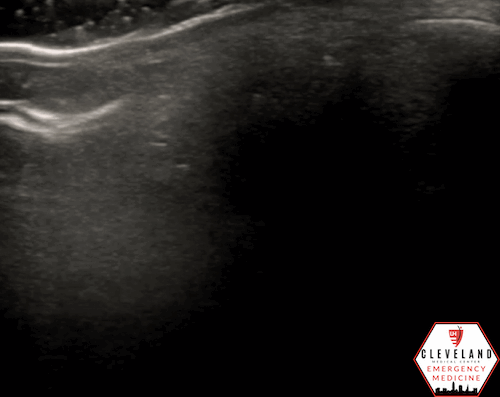

Figure 4. Sagittal and transverse views of a retrobulbar hyperechoic spot (8).